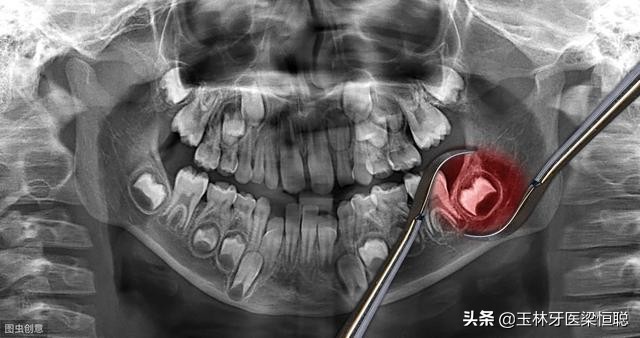

由于大多数智齿是前倾阻生的,约呈45度角顶在第二磨牙上,从而形成一个牙冠夹角,容易嵌塞食物,久之导致第二磨牙龋坏,甚至牙髓炎,就算没有那么严重也会影响第二磨牙的寿命。

2、龋齿。位置不正的智齿与第二磨牙之间容易积存食物残渣,而且不易清洁,一般数月可形成龋齿,直接破坏牙体组织。